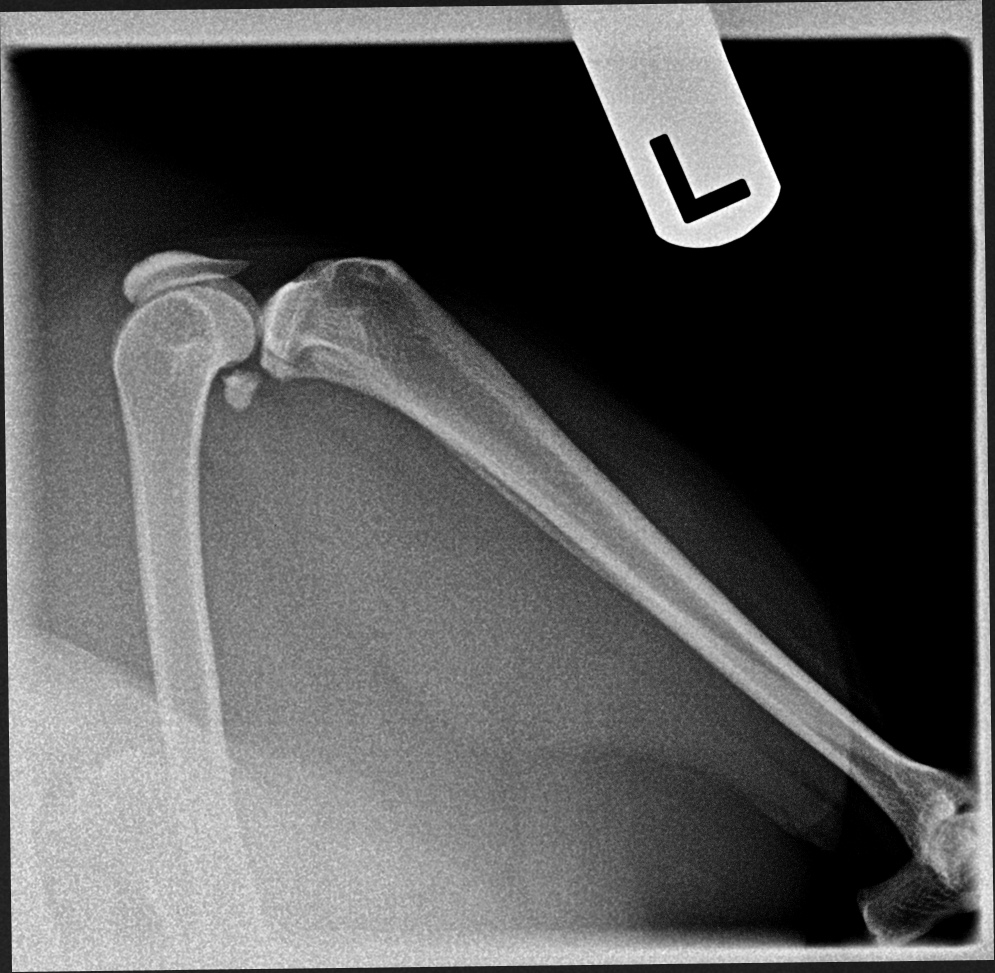

The images from the source dataset had issues and needed to be consolidated into a more usable framework. These issues were mostly due to inconsistencies in practices of radiographers and movement by the animals during radiography that resulted in radiographs with incomplete data, inconsistent image quality, such as varying contrast, brightness and positioning of point of interest or images that failed to meet the prerequisite conditions for this task. Examples of difficult data are shown in Fig. 5.